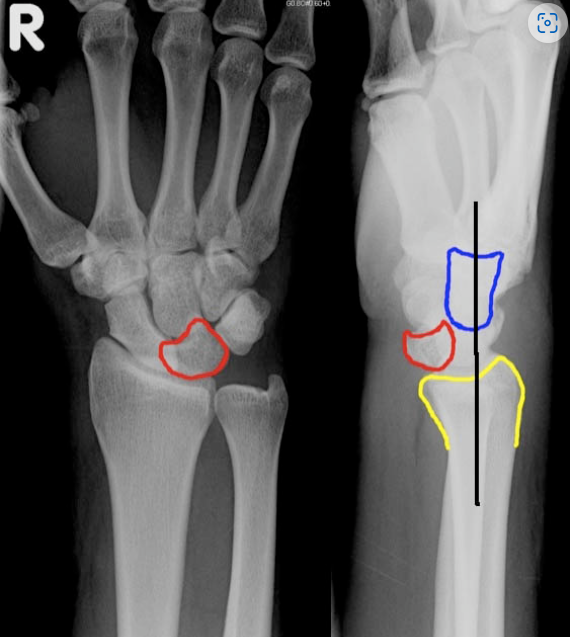

Radial Fracture Reduction Parameters

A

Acceptable parameters for radial Fractures:

* Dorsal tilt < 10 degrees

* Radial shortening (on PA view): loss of >2mm more should be corrected

* Radial shift (on PA view): any shift should be corrected

* Radial inclination (on PA view): <15 degrees

* Volar tilt (on lateral view): <20 degrees (normal volar tilt is 10–25 degrees).

* Dorsal displacement

Lines on XR indicating

Dotted line C - Radial shortening

Line B - radial inclinaiton or ulna tilt

Line D -radial tilt